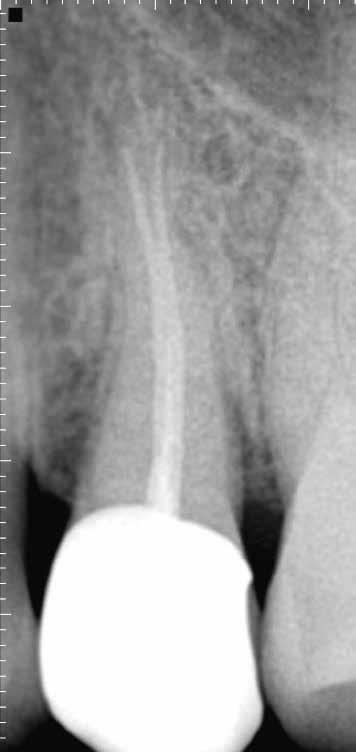

1. a-n. ábrák: Preoperatív CBCT-felvétel a bal alsó 6-os (3.6) fogról. Az axialis (a), coronalis (b) és sagittalis (c) nézeteken a mezialis és distalis gyökerek apicalis harmada körül sugáráteresztő zóna és ép buccalis corticalis csont látható. Egy olyan sablont terveztünk, amely jelezte a csontablak határait az apicalis terület pontos elérése érdekében (d). A mikrosebészeti bevatkozás során a sablont a helyére illesztettük (e), a csontablak határait megjelöltük (f) egy Piezotome CUBE LED kézi-darabba fogott fűrésszel, majd kivágtuk és eltávolítottuk (g és h) az apicalis területhez történő hozzáférés, illetve a mezialis és distalis gyökerek rezekciójának, retrográd preparációjának és retrográd gyökértömésének elvégzése érdekében (i). Végezetül a csontablakot visszaillesztettük és kollagén szivaccsal stabilizáltuk (j). A műtét után közvetlenül készített röntgenfelvétel a 3.6-os fogról (k). A kétéves kontroll során készített CBCT-felvétel: axialis (l), coronalis (m) és sagittalis (n) nézetek.

Egy 63 éves páciens korábban már kezelt bal alsó első nagyőrlőfogából (3.6) eredő mérsékelt fájdalom miatt kereste fel rendelőnket. A kórtörténetében panasza szempontjából releváns információ nem szerepelt. Az elkészült CBCT-felvételen a korábbi kezelések során észre nem vett, jelenleg feltáratlan meziobuccalis csatornát, valamint a mezialis és distalis gyökerek körül kialakult periapicalis elváltozást, és ezt a léziót borító intakt buccalis corticalis csontlemezt láttunk.

Klinikai vizsgálat során vertikális kopogtatási érzékenységet jelzett. A fog körül mérhető szondázási mélység és a fogmobilitás fiziológiás volt. A CBCT-felvételen nem észleltünk a csontos regeneráció megindulására utaló jeleket (1. a–c. ábrák). A korábban gyökérkezelt, gyökértömött és revideált 3.6-os fog esetében az alábbi diagnózis került felállításra: periodontitis periapicalis symptomatica. A panaszokat okozó fog további ellátása során navigált endodonciai mikrosebészetet kívántunk alkalmazni. Az alsó állcsontról intraorális szkent (TRIOS, 3Shape) készítettünk, és a felszíni topográfiát tartalmazó STL fájlt, valamint a CBCT-felvétel készítése során nyert DICOM fájlokat a Blue Sky Bio szoftver segítségével egyesítettük. A sebészi sablon megtervezésére az így kapott háromdimenziós képet használtuk. A sablon kialakítása során arra törekedtünk, hogy a sablon egyértelműen meghatározza a gyökércsúcsi terület eléréséhez szükséges csontablak határait (1. d. ábra)